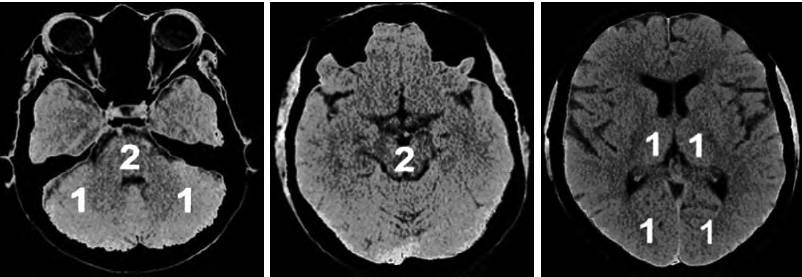

CT灌注成像是用来识别AIS后缺血半暗带的另一种成像技术,通过对各循环参数的判定来识别缺血半暗带。CTP常见的参数有:CBF、CBV、相对脑血容量(rCBV)、MTT、达峰时间(TTP)、相对平均通过时间(rMTT)、相对延迟时间(rDT)。随着CT对团注造影剂的扫描形成信号清除曲线,继而生成半定量CBV和CBV图。当缺血更为严重时,则CBV萎陷。

CT灌注成像对于梗死核心灶标记为CBV降低的区域,CBF与MT T以低于界定的阈值(CBV<2 ml/100 g、CBF<20 ml/100 g/min及MTT>8 s)来显示脑的异常灌注区。缺血半暗带为脑梗死核心区与异常灌注区域之间的差异区域(图3)。

5.2.3 磁共振成像DWI-PWI不匹配区

MRI PWI常采用动态磁敏感对比增强技术,通过对比剂团注追踪技术进行动态增强扫描,依靠对比剂磁化率改变引起信号变化的原理成像。经处理后可得出相应灌注成像的参数如CBF、CBV、MTT及TTP等。研究表明,CBF下降和MTT延长是组织缺血的相对敏感指标,但存在过分估计最终梗死体积的可能性;TTP图像上脑灰质、白质之间无明显区别,能够清楚显示病变的范围和边界。虽然目前识别缺血半暗带的方法有多种,但MRI DWI与PWI不匹配区是急诊过程中判断缺血半暗带较切合实际的方法(图4)。一项回顾性研究认为,PWI的病灶面积是DWI病灶面积的2.6倍时早期再灌注的治疗效果最好。

图4 磁共振成像DWI-PWI不匹配区影像 注:A:磁共振DWI序列:高信号的梗死区(粉色标记区);B:磁共振PWI序列:梗死区周围的缺血半暗带(绿色标记区)。DWI:弥散加权成像;PWI:灌注加权成像